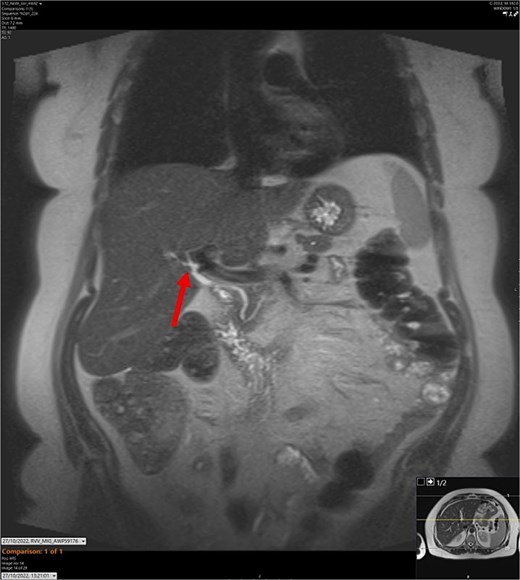

CT abdomen-pelvis scan in coronal view. The arrow points to where we expect the gallbladder to be seen, but it cannot be visualized on the scan.

On admission, the patient’s blood tests showed normal inflammatory markers, liver function markers, and amylase (Table 1). The patient underwent an abdominal ultrasound scan, which did not visualize gallstones or the gallbladder. A computerised tomography (CT) abdomen-pelvis scan was done, and the gallbladder could not be visualized (Figs 1 and 2). Further investigations, which include a magnetic resonance cholangiopancreatography (MRCP) and hepatobiliary iminodiacetic acid (HIDA) scan, confirmed a gallbladder bud with an intact biliary tree (Figs 3–6). The patient denied a history of a cholecystectomy. She was diagnosed with gallbladder agenesis.